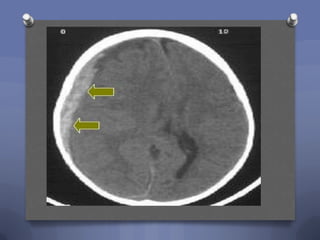

Case 2

O A 5 year old girl falls from a second story

window. You find the following on CT scan:

What is your diagnosis?

1. Epidural hematoma

2. Subdural hematoma

3. Diffuse axonal injury

4. Contusion

Epidural Hematoma

O Caused by tears of

meningeal vessels

O Convex shape

O Often associated bone

fracture (up to 75%)

O Typically few hours of

lucidity followed by rapid

deterioration

O Need close observation

and often surgical

evacuation

O Good prognosis if

recognized and treated